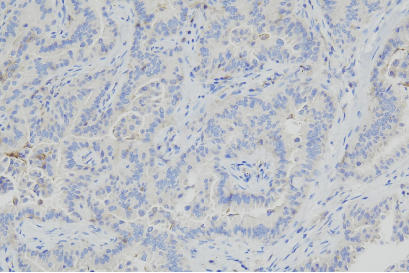

案例展示

抗体在肿瘤组织中显示出明确的特异性染色信号,定位清晰。

在腺上皮组织中可见目标蛋白的阳性表达,染色分布具有组织特异性。